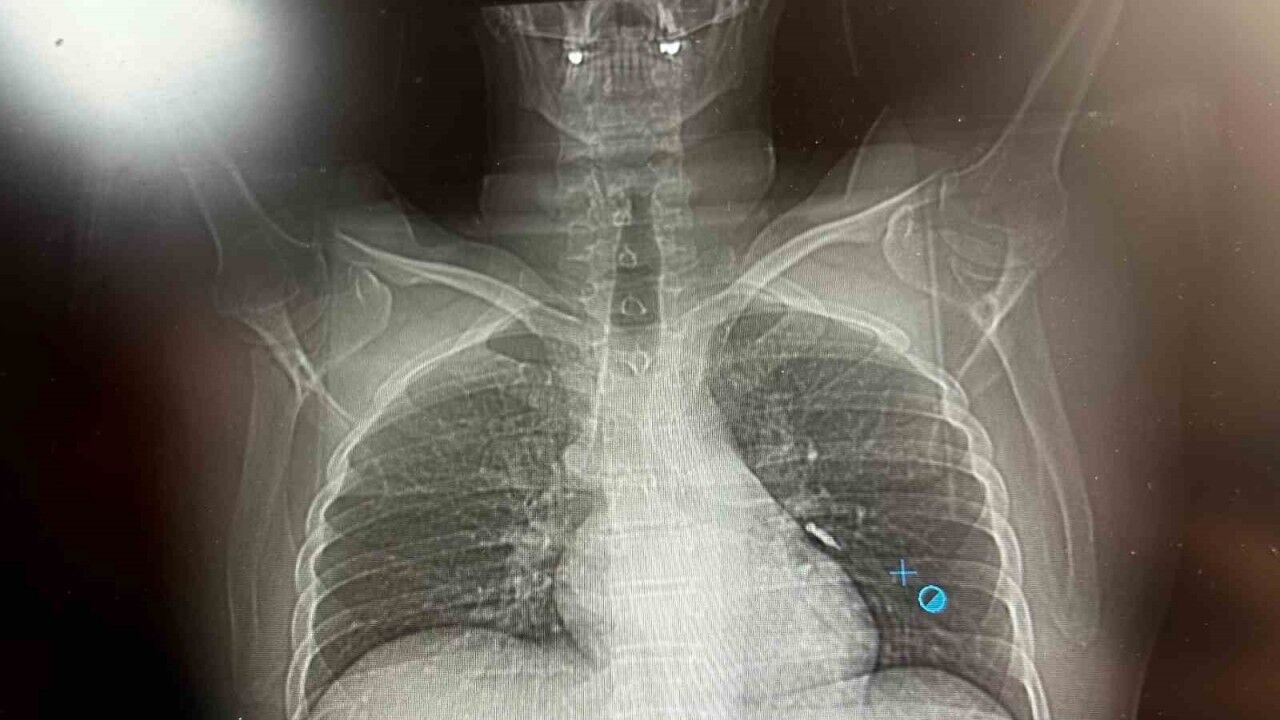

Göğüs Cerrahisi uzmanları Dr. Sadullah Aksoy ve Dr. Beniz İrem Ersoy Şığva tarafından hastaya bronkoskopi işlemi uygulandı. Sol akciğerin üst lobunda saplanmış şekilde tespit edilen vida, vidalı yapısı ve bulunduğu konum nedeniyle güçlükle yerinden oynatılabildi. Yapılan uzun ve titiz müdahale sonrası vida yerinden çıkarılamasa da hasta bir süre sonra geçirdiği öksürükle birlikte implant vidasını midesine gönderdi. Vida, daha sonra doğal yollarla vücuttan atıldı.

Konuya ilişkin konuşan Göğüs Cerrahi Op. Dr. Sadullah Aksoy, bir diş merkezinde diş tedavisi sırasında hastanın çenesine yerleştirilen implantın vida kısmının işlem esnasında yanlışlıkla aspire edildiğini belirtti. İlk olarak hastanenin ek hizmet binasında çekilen tomografi sonucunda, vidanın sol akciğerin hava yollarının yaklaşık dördüncü dalına kadar ilerlediği tespit edildiğini ifade eden Op. Dr. Aksoy, "Geçtiğimiz cumartesi günü öğle saatlerinde tarafımıza ulaşıldığında, hastanın Van Eğitim ve Araştırma Hastanesi’ne yönlendirilmesini istedik. Burada acil bronkoskopi planı yapılarak hasta kabul edildi. Hasta geldiğinde genel durumu iyiydi; solunumunu tamamen engelleyen bir bronş tıkanıklığı söz konusu değildi. Aynı gün hastamızı hazırladık. Bronkoskopi sırasında, implant vidasının sol üst lobun anterior segment bronşuna saplanmış pozisyonda olduğunu gördük. Üroloji bölümünde taş çıkarma işlemlerinde kullanılan cihazla müdahale ettik. İlk denemede implant tamamen çıkarılamadı ancak yerinden oynatılabildi. Bunun üzerine bir süre bekleyip hastayı yeniden bronkoskopi için hazırlamaya başladık. İşlem yaklaşık 3,5-4 saat sürdü ve saat 18.30 civarında hasta işlemden çıkarıldı" dedi.

Daha sonra hasta için yeniden bronkoskopi planladıklarını ancak bu süreçte hasta şiddetli bir öksürük geçirdiğini anlatan Aksoy, "Şiddetli öksürük sonrası yapılan kontrol akciğer filminde implant vidası görünmedi. Bunun üzerine toraks ve batın BT (bilgisayarlı tomografi) görüntülemesi istedik. Sonuçlarda implantın akciğerden çıktığı ve vücutta herhangi bir yerde bulunmadığı tespit edildi" diye konuştu.